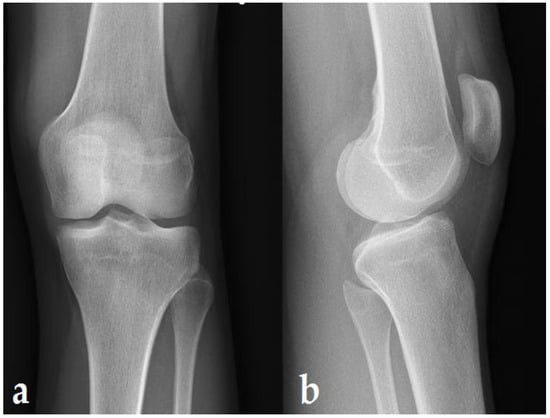

2. Case Report

3.1. Knee Lesions Encountered

3.1.2. Osteonecrosis Lesions of the Knee